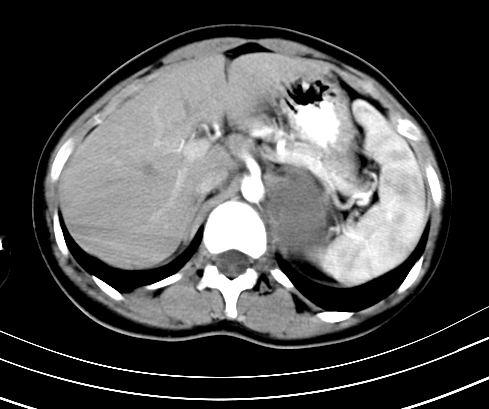

动脉期